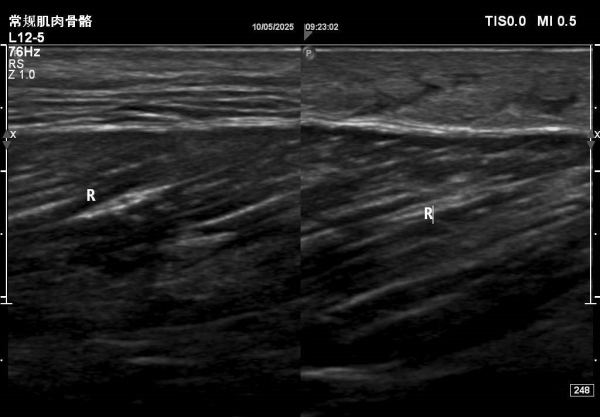

大腿包块—病例

患者大腿远端浅表可见一包块隆起,自述半月前出现红肿,目前未见明显红肿,触摸感觉微痛。

根据病情考虑可能蚊虫叮咬水肿。大家考虑是什么?有没有专家给看看,是什么?谢谢。